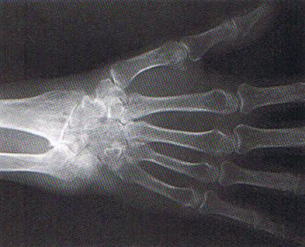

手首の腫れたリウマチの患者さんが、急に指が伸びなくなれば診断がつきます。レントゲン検査で手首の骨に異常が見られます。

リウマチによる手の障害(1)伸筋腱断裂 診断